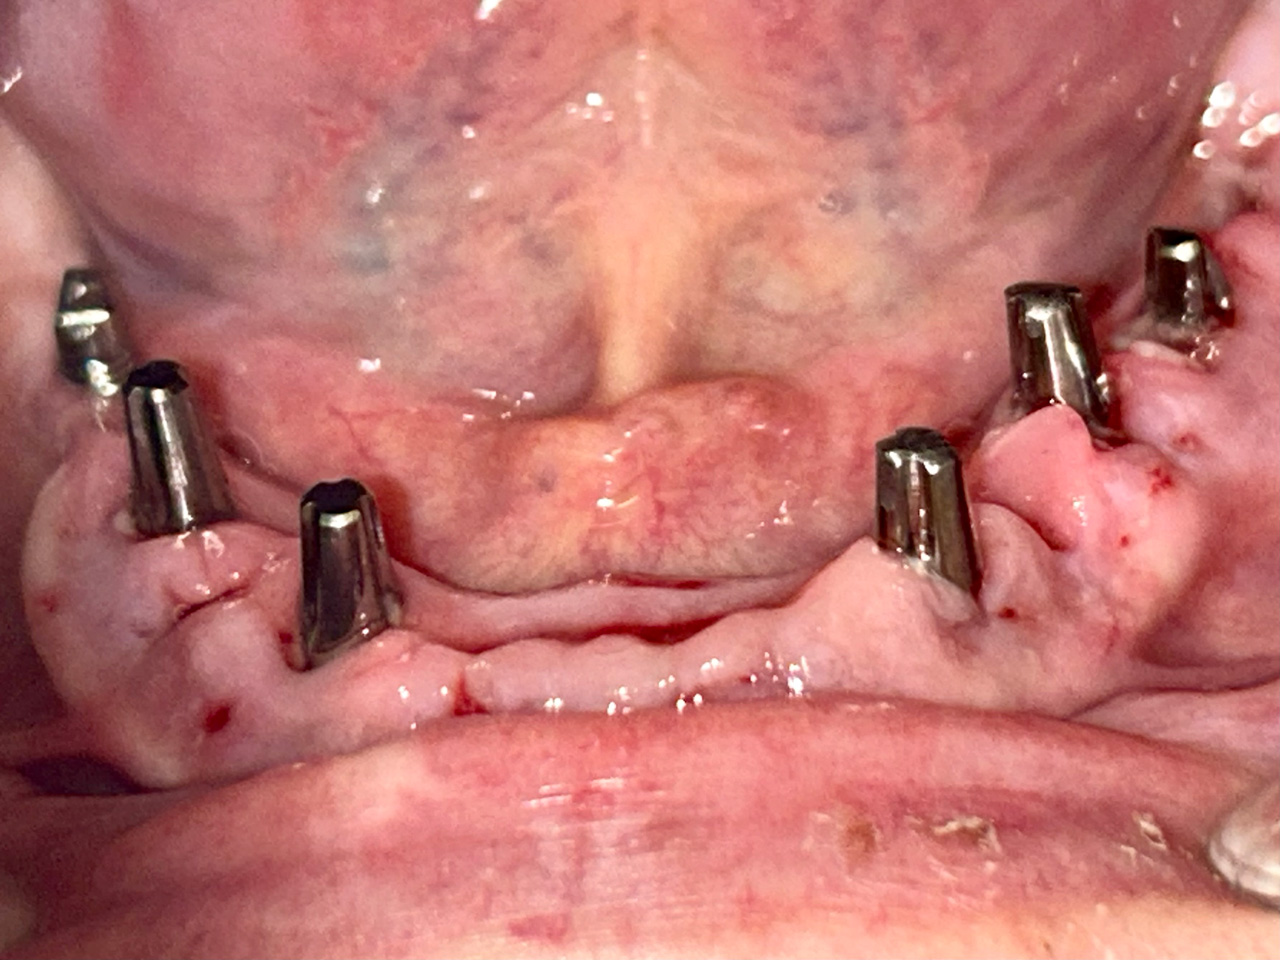

Teljes fogatlanság helyreállítása 2 nap alatt

Teljes fogatlanság helyreállítása 2 nap alatt azonnal terhelhető svájci IHDE implantátumokkal és PMMA műanyag hidakkal. Intraorális szkennerrel vettünk lenyomatot az implantáció után, és erre a digitális mintára készítette el a fogtechnika a hidak digitális tervezését, majd faragta ki műanyagból. Ezt a gyors munkát az azonnal terhelhető implantátumok és a digitális lenyomat, tervezés segítségével tudtuk megcsinálni mindössze 2 nap alatt. Dr. Kelemen Péter és a Symbion Fogtechnika munkája.